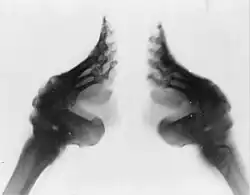

Primero cada pie se bañaba y sumergía en una mezcla caliente de hierbas y sangre animal: esto se hacía con la intención de ablandar el pie para ayudar al vendado. Luego las uñas se cortaban al ras para prevenir que al crecer perforasen la planta del pie (ya que después del vendado la punta de los dedos quedaba apuntando a la planta) y provocaran infecciones. Las vendas de algodón de 3 metros de largo y 5 centímetros de ancho eran preparadas hundiéndolas en la misma mezcla de hierbas y sangre animal. Para permitir que el tamaño del pie se redujese, los dedos de cada pie eran doblados y presionados con fuerza contra la planta del pie hasta lograr romperlos.

Los dedos rotos eran mantenidos apretados contra la planta del pie mientras este era estirado hacia abajo, formando línea recta con el resto de la pierna. El arco se rompía a la fuerza. Las vendas eran atadas repetidamente en forma de ocho, empezando en el interior del pie en la zona del empeine, pasando sobre los dedos, luego bajo el pie y alrededor del talón. Los dedos recién fracturados eran apretados firmemente contra la planta. Con cada vuelta de la venda, el vendaje se apretaba cada vez más estrechando el empeine y el talón entre sí. Esto provocaba que el pie roto se doblase en el arco y los dedos quedasen bajo esa doblez.

Al principio del vendado muchos huesos del pie a quedaban rotos durante años. Con el tiempo, los huesos se acababan soldando, sobre todo cuando el tejido óseo se endurecía tras la etapa de crecimiento. Aún después de que los pies sanaran de infecciones eran propensos a quebrarse nuevamente, especialmente cuando la niña pasase por sus años adolescentes y sus huesos estuvieran todavía blandos. Las mujeres adultas tenían más probabilidad de quebrarse las caderas y otros huesos debido a caídas, pues su caminar era inestable y les costaba ponerse de pie desde una posición sentada.[20]